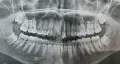

Здравствуйте! Подскажите, пожалуйста, у моей дочери (15 лет) есть один кривой зуб на нижней челюсти, он уходит назад примерно на 5 мм. Обязательно ставить брекет-систему? Есть ли брекет-система, которую будет не видно? Большое спасибо!

Добрый день. Скорее всего ребенку необходимо установить брекет-систему.

Да, конечно, можно установить лингвальную брекет-систему, которая устанавливается на внутреннюю часть зубов и визуально не заметно!

25 лет. Неправильный прикус, нижние зубы выступают вперед, верхние передние зубы кривые из-за клыков, которые их сдвинули. Можно ли поставить брекеты и будет ли от них польза в таком возрасте? Еще слышала, что после того как снимаешь их, зубы кривятся снова.

Сколько нужно носить брекеты, чтобы исправить три передних верхних зуба в 23 года?